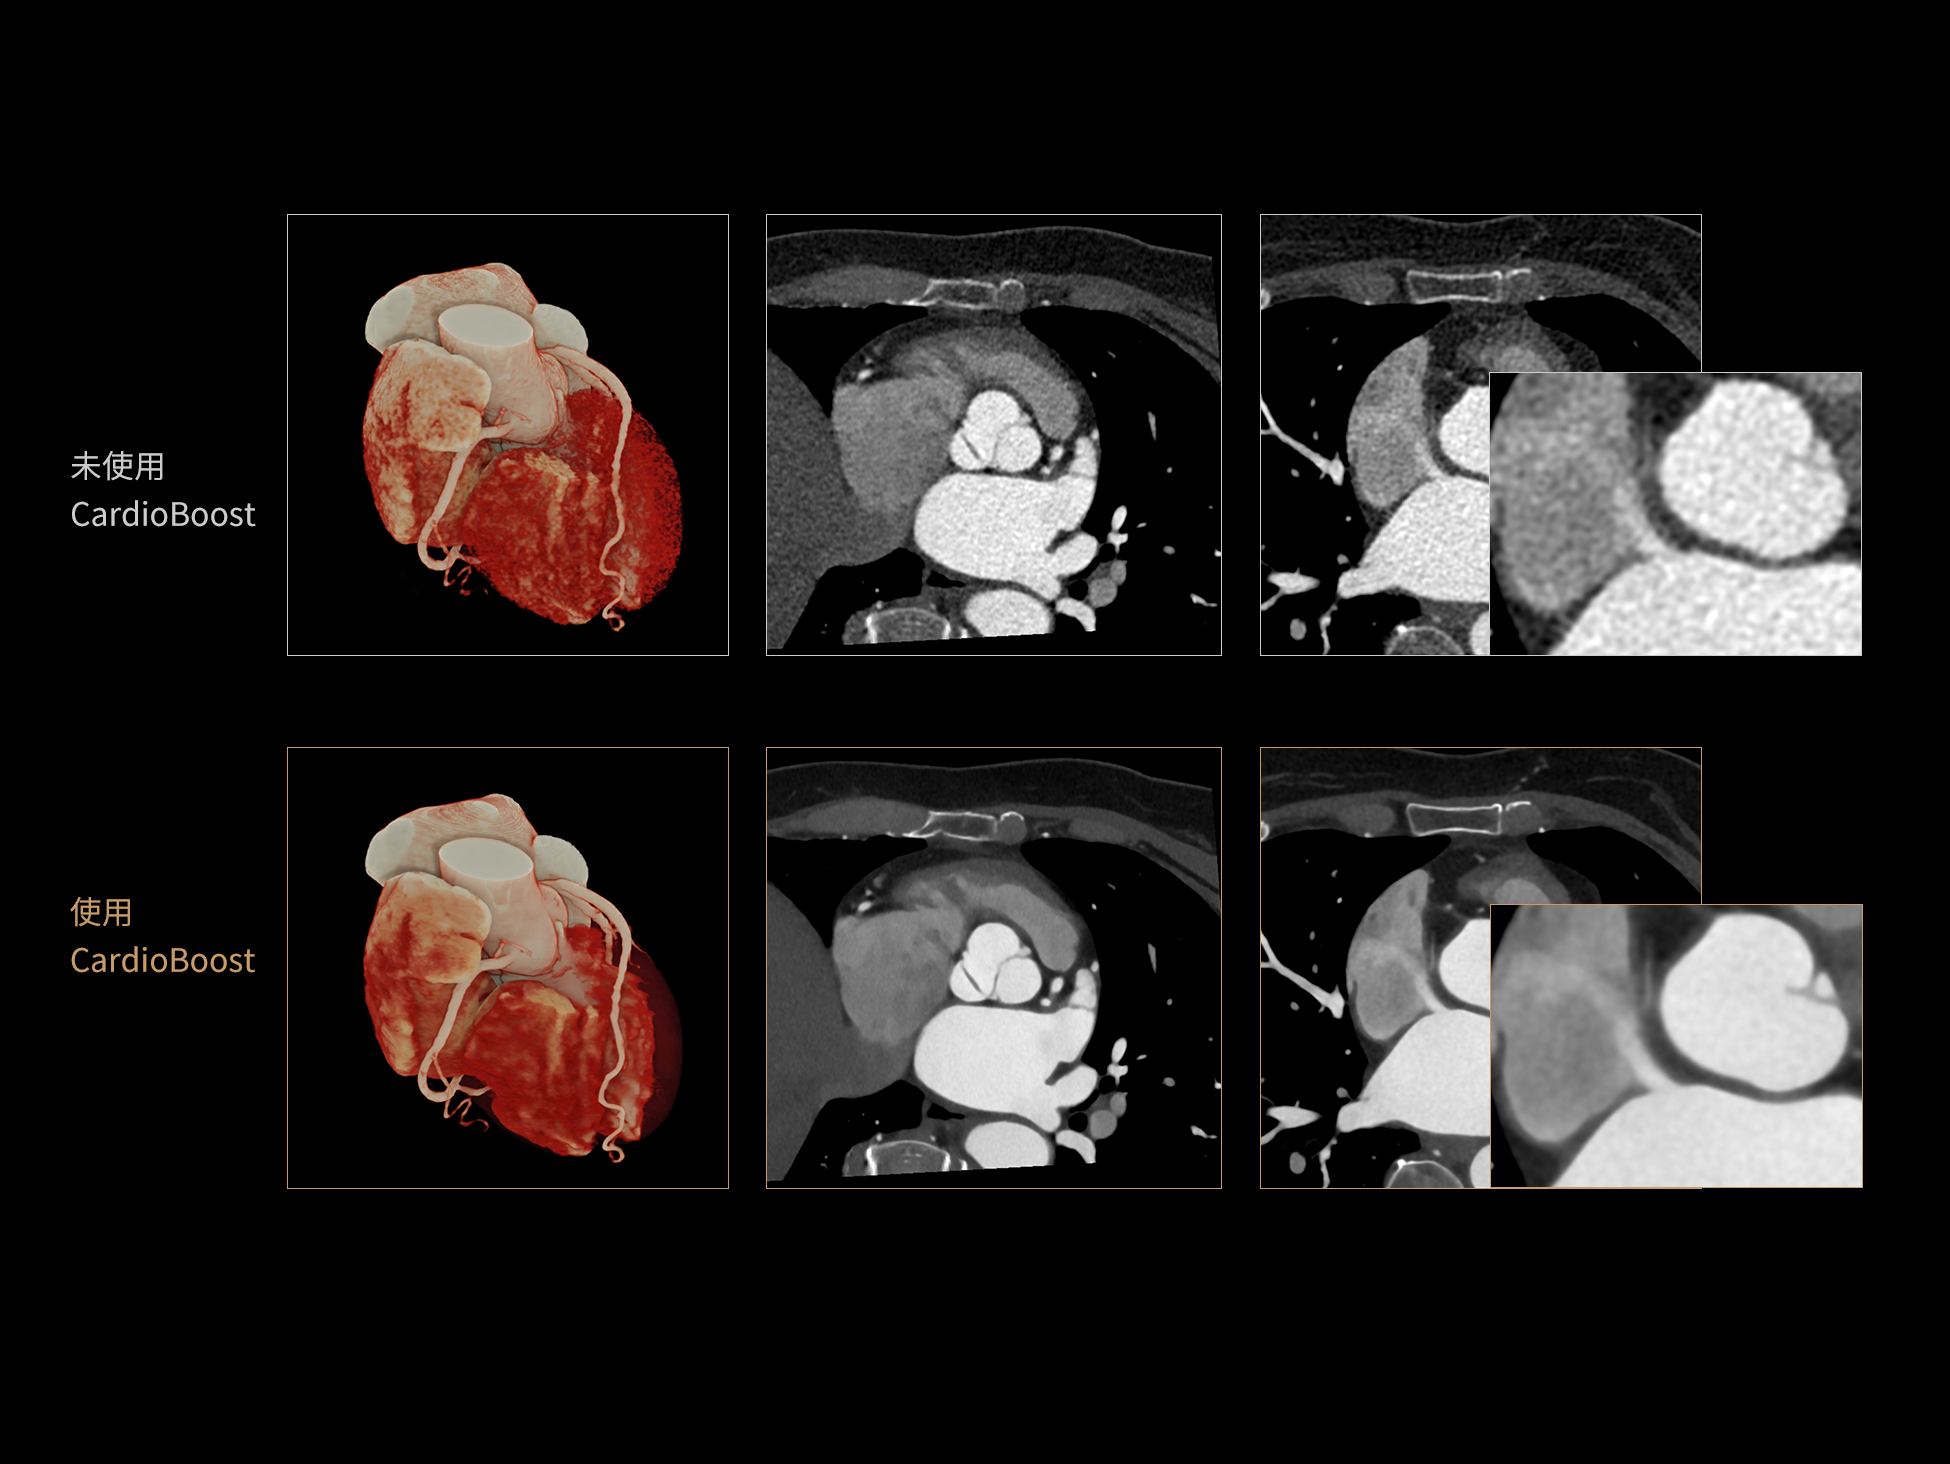

CardioBoost:专属网络设计,重塑心脏影像表现

目前心脏的 CT 检查还存在辐射剂量偏高、空间分辨率不足、 致密钙化伪影影响冠脉狭窄程度评估等方面的限 制[1][2]。CardioBoost 技术专为心脏 CT 高清成像而开发,通过 3D 神经网络的深度学习技术,利用先进的注意力机制在识别关键成像特征方面的出色表现,能够精确地聚焦于斑块、支架以及微小血管等关键细节,清晰展示这些结构与冠脉血管的边界,从而显著提高诊断的准确性,并提升医生的诊断信心。创新的 CardioBoost 心脏图像重建算法,不仅实现了图像清晰度的提升和伪影的去除,更能在减少辐射剂量的同时,保证心脏图像的高质量和图像纹理的自然。

CardioBoost核心创新

采用 3D 神经网络的空间结构优势与精细的组织分类能力,CardioBoost 技术优化了组织对比,高清展示血管斑块,使斑块与血管边缘的轮廓清晰可辨,提升斑块诊断与评估的精确性。

借助 3D 神经网络设计、空间注意力机制聚焦与特征强化作用,CardioBoost技术提升图像的空间分辨率,实现冠脉支架的高清成像,对支架形态与管腔通畅度的评估更精准。

CardioBoost 整合先进的 3D 神经网络和空间注意力机制,大幅增强数据处理的速度与精确度。该技术能有效抑制由致密钙化引起的晕状伪影,清晰展现钙化斑块的原始结构和大小,对冠脉狭窄的评估更加精确可靠。

对比度强化模块

分辨率强化模块

伪影抑制模块

超真实渲染(Hyper Realistic Rendering,HRR)可将医学影像数据转化为高度真实、细节丰富的三维数字可视图像。相比传统VR渲染,HRR在解剖结构与图像细节的还原上更为精准,助力临床直观地理解病灶特征与组织关系,更加适用于术前规划、教学演示及患者沟通。

HRR超真实物理渲染:精准还原解剖细节的三维可视化技术